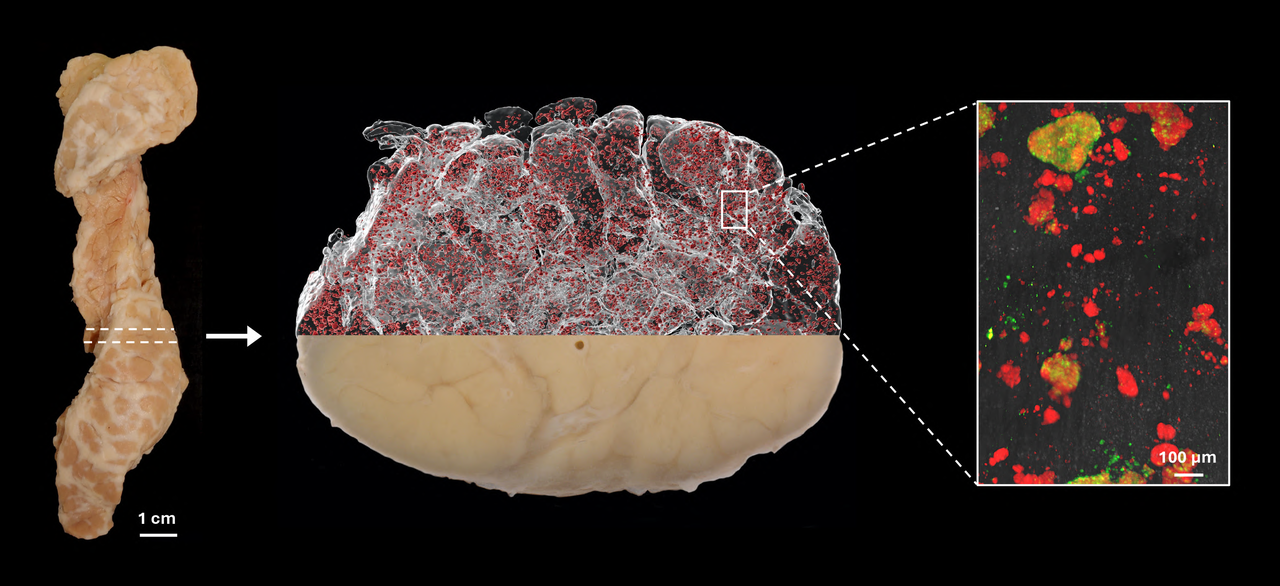

Illustrationen visar hur en hel bukspottkörtel (t.v.) från en avliden donator kan färgas in med antikroppar för olika celltyper och avbildas med optisk projektionstomografi (i mitten, Insulinfärgade öar i rött). Den kan sedan studeras i högre upplösning med ljusfältsmikroskopi (t.h.). Det röda är insulin och det gröna glukagon.

Filmen visar en mänsklig bukspottkörtel från en icke-diabetisk donator (〜15cm lång). Den innehåller 2.21 miljoner insulinproducerande Langerhanska öar (röda) med en total volym av 1,17 kubikcentimeter.

Då de Langerhanska öarna endast utgör någon enstaka procent av bukspottkörteln, samtidigt som de förekommer i så stor mängd, har de historiskt sätt varit mycket svåra att studera in situ, det vill säga på plats i bukspottkörteln. Forskarna har i de flesta fall fått studera vävnadssnitt som endast ger en tvådimensionell bild av en mycket liten del av organet. Umeåforskarna har använt optiska 3D-tekniker där olika celltyper kan märkas in med färgade antikroppar.

– Genom att dela upp hela organet i mindre delar möjliggör vi för antikropparna att komma dit de ska. Då vi vet var varje bit kommer ifrån kan vi sedan, efter att vi skannat de olika delarna individuellt, “bygga ihop” hela bukspottkörteln igen i en dator. Detta gör att vi kan utföra en uppsjö av beräkningar samt studera vilka celltyper som finns och var, då vi vet 3D-koordinaterna, volymen, formen och andra parametrar för varje infärgat objekt i hela organet.